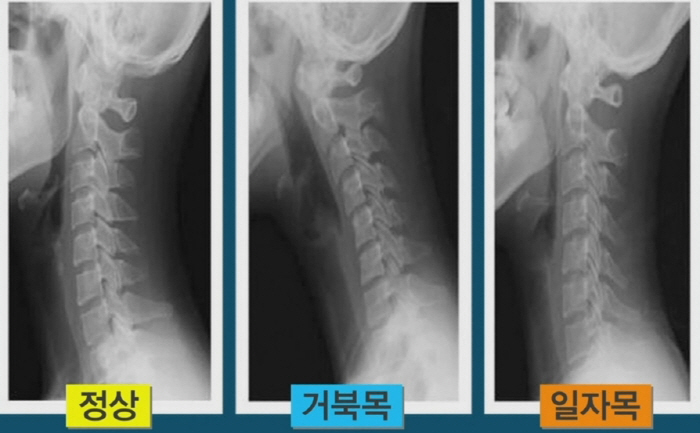

목은 목뼈(경추) 7개로 되어 있다며 뼈와 뼈 사이에 디스크가 있습니다. 디스크는 기립 자세에서 수직으로 끼치는 압력을 분산하고 목이 동작할 때 관절 역할을 합니다. 나이가 들면 아무라도 피부 탄력이 감퇴하여 주름이 생기듯 척추의 디스크도 수분 함유하고 있는 분량이 쇠퇴하여 긴장되고 이로 인하여 충격을 섭식하고 압력을 분산시켜서하는 기능이 저하되요.

목디스크는 왜 생기는 걸까요? 사람들이 나이가 들면 디스크의 수분 성분인 수핵의 수분함유 분량이 떨어뜨리여 탄력이 감소하게 되고 해로운 자세나 사고 등의 바깥 부분적인 자극에 의해 디스크가 밀려나 목디스크 질환의 이유가 되는 것이 된다고 합니다. 평범할 때 생활하면서 틀린 습관, 목에 가해진 충격 등에 의해 일어나기 쉽다고 하고요.